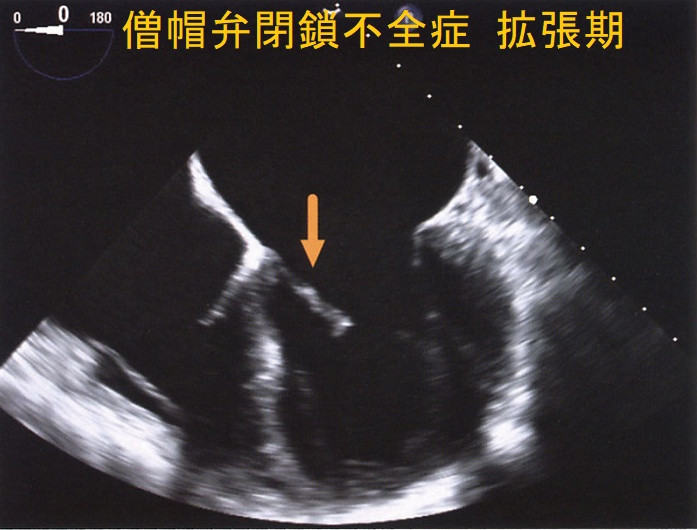

僧帽弁閉鎖不全症(MR)は、

- 僧帽弁破壊:動脈硬化、リウマチ熱による僧帽弁の石灰化、感染性心内膜炎

- 僧帽弁逸脱:閉塞性肥大型心筋症、甲状腺機能亢進症の30%に起こる

甲状腺機能亢進症/バセドウ病、甲状腺機能低下症/橋本病(下記)

などが原因となります。

甲状腺機能亢進症/バセドウ病、甲状腺機能低下症/橋本病では僧帽弁腱索/乳頭筋断裂の頻度が高い(Endocr Rev. 2005;26(5):704–728.)。

自己免疫性に粘液多糖類が蓄積し、僧帽弁の粘液水腫性変化が生じます

- 甲状腺機能亢進症/バセドウ病の33%

- 甲状腺機能低下症/橋本病の36%

(Thyroid. 2002 Mar; 12(3):193-5.)

特に循環血液量・心拍出量が増加する甲状腺機能亢進症/バセドウ病では、僧帽弁腱索/乳頭筋断裂を引きおこす危険性が高い。(J Endocr Soc. 2018 Sep 17;2(11):1246-1250.)[Endocrinol Diabetes Metab Case Rep. 2022 Jul 1;2022:22-0298.]

僧帽弁腱索/乳頭筋断裂がなく、粘液腫性変性による中等度から重度の僧帽弁閉鎖不全症(MR)なら、甲状腺機能の正常化に伴い改善する可能性があります。[BMJ Case Rep. 2021 Feb 4;14(2):e239626.]